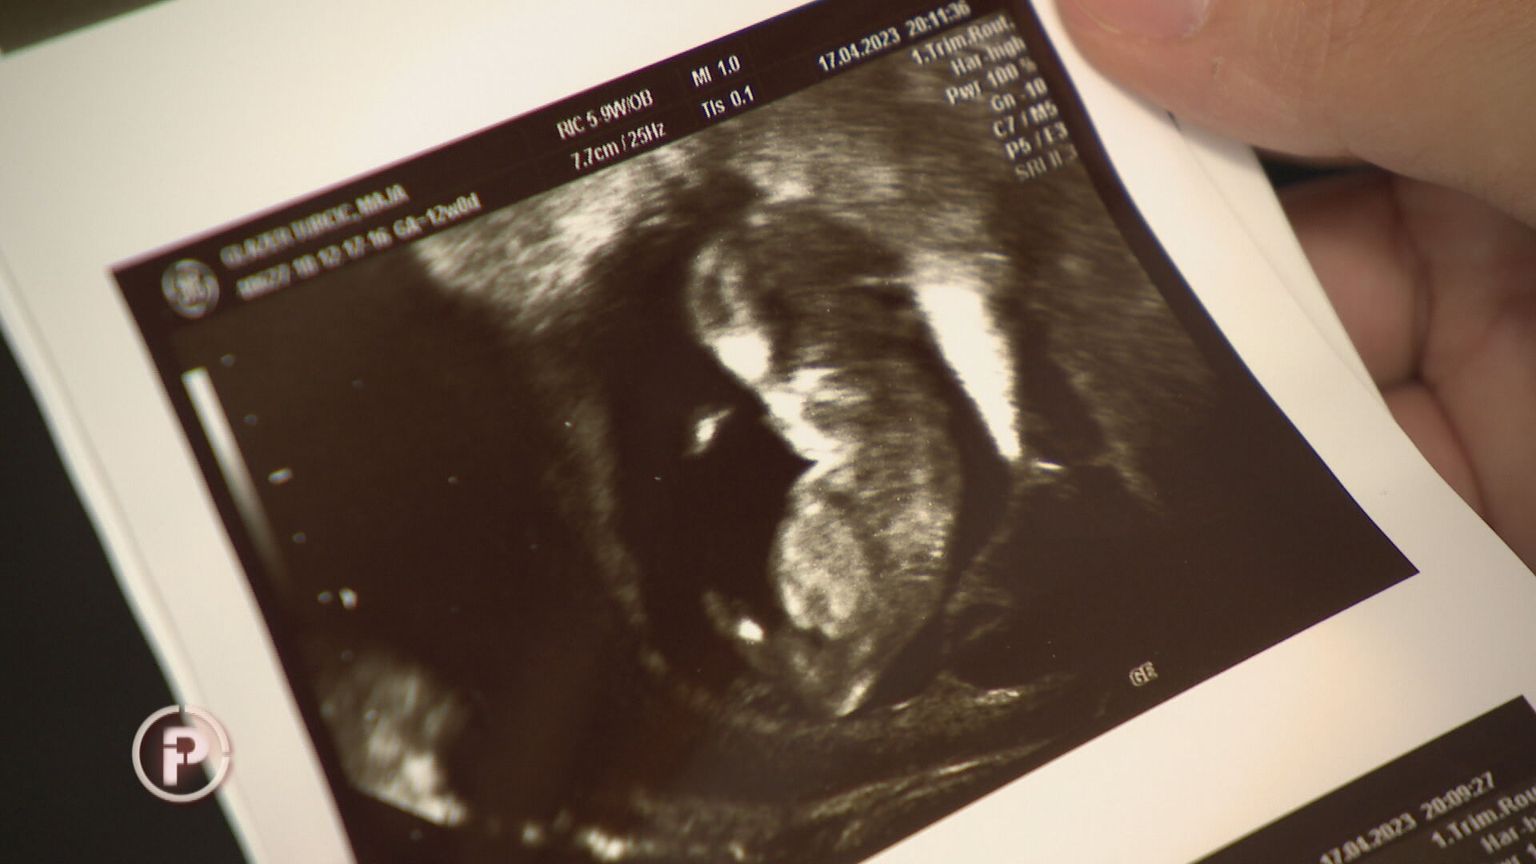

Kako je trudnica dobila injekciju za pobačaj? DNEVNIK.hr doznaje - Ministarstvo šalje inspekciju u bolnicu

Godinama su tražili pomoć, a onda se dogodila tragedija na koju su upozoravali: "Ovo je ludost. Kako su to dopustili?"